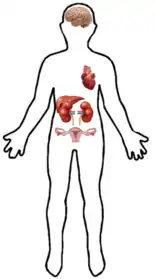

Both the human and the mouse genes contain a polymorphic (CA) repeat in their 3'UTR. Specifically, human tissue presents two, 4.2- and 3.6-kb, EHD3 RNA species. While the gene is highly expressed in heart and brain, it is moderately expressed in kidney, ovary, liver and placenta.

EHD3 protein has been found in humans and mice. It can be mainly found in human heart and brain, as well as kidney, ovary and liver.

The lack or malfunction of this protein in the human body can cause some diseases such as heart failure[19] or a depressive disorder. Losing EHD3 is also known to be an early step towards glioma formation.